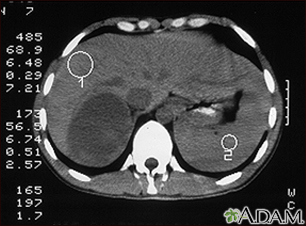

Adrenal Tumor - CTBackAdrenal Tumor - CTCT scan of the upper abdomen in a person with a right adrenal mass. The adrenal glands are located above the kidneys. E-mail FormEmail ResultsName:Email address:Recipients Name:Recipients address:Message: